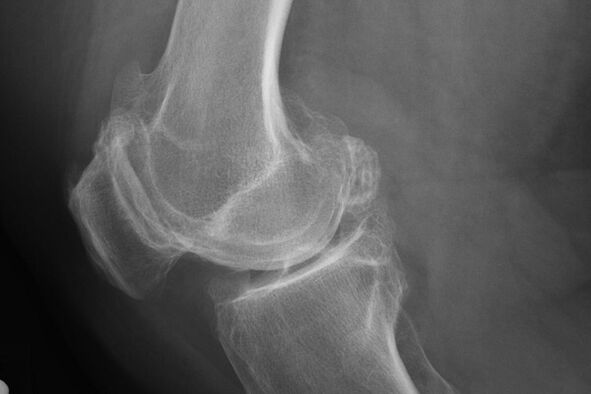

In de regel treedt de diagnose van de ziekte in dit stadium per ongeluk voor, tijdens een X -Ray. Daarop kan de arts enkele onregelmatigheden op kraakbeen opmerken. Het is ook mogelijk om het lumen tussen de delen van het gewricht te beperken.

X -Ray helpt bij het identificeren van afwijkingen in kraakbeen.

Na het onderzoek schrijft de arts de radiografie van de patiënt voor. Dit is de belangrijkste methode om artrose van het kniegewricht van elke mate te diagnosticeren.

X -Ray geeft de arts een idee van de veranderingen die zich voordoen in het kraakbeen van het gewricht. In sommige gevallen mag de beginfase echter niet op de foto worden gedefinieerd.

Indien nodig kan de arts een herhaalde doorgang van een röntgenfoto's of berekende en magnetische resonantietomografie voorschrijven.